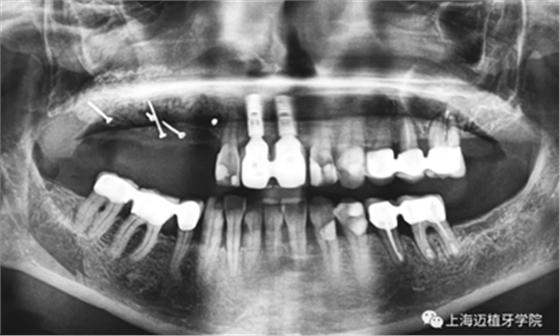

術(shù)前照,生物骨材料植骨失敗,植體暴露,生物骨材料沒(méi)有成骨(如圖),垂直向和水平向都受到感染